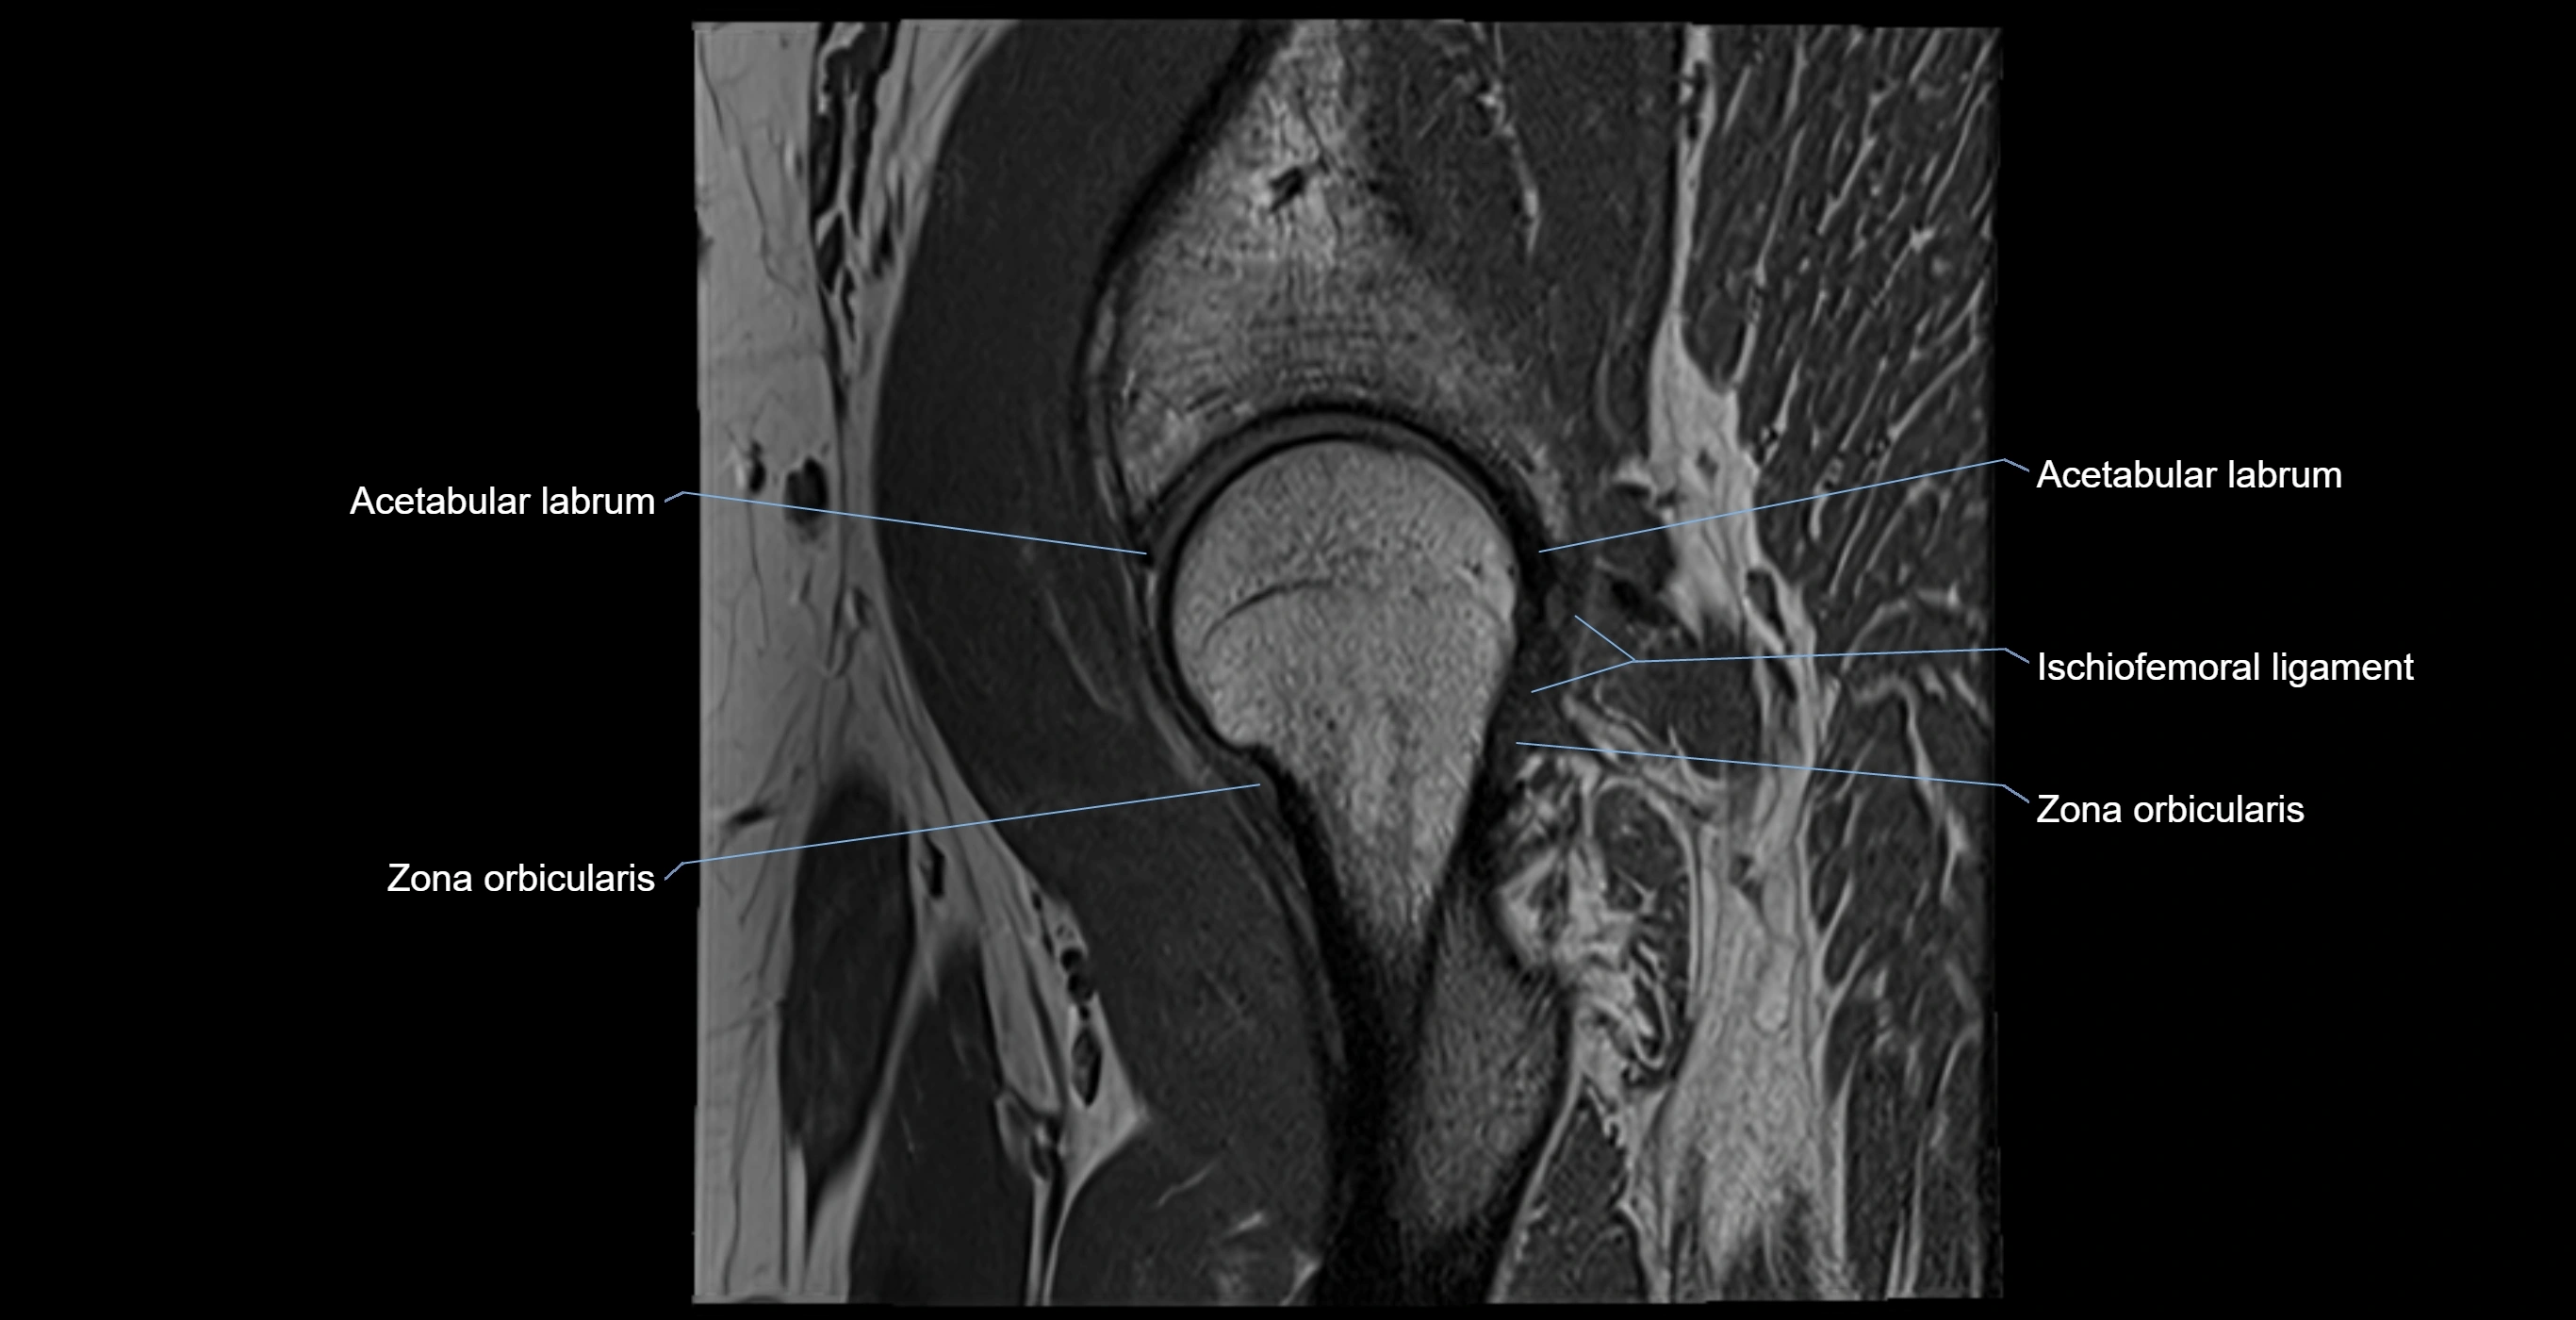

The acetabular labrum is a fibrocartilaginous ring that surrounds the rim of the acetabulum in the hip joint. It deepens the hip socket, increases joint stability, and maintains a suction seal that preserves negative intra-articular pressure. Structurally, the labrum transitions from hyaline cartilage of the acetabulum to dense fibrocartilage at its free edge.

It is triangular in cross-section, with its base attached to the acetabular rim and its apex projecting toward the femoral head. The labrum is most robust superiorly and anteriorly, where load bearing is greatest, and relatively thinner inferiorly.

Structure and Relations

• Superior and anterior labrum: thickest portions, stabilizing against anterior dislocation

• Inferior labrum: blends with the transverse acetabular ligament bridging the acetabular notch

MRI Appearance

T1-weighted images:

• Labrum: low signal intensity (dark)

• Surrounded by intermediate signal joint fluid (bright on arthrogram)

• Tears: linear or focal areas of intermediate-to-high signal interrupting labral continuity

T2-weighted images:

• Joint fluid: bright, making labral tears visible as fluid extending into or around labrum

• Degeneration: may show areas of increased signal within labrum